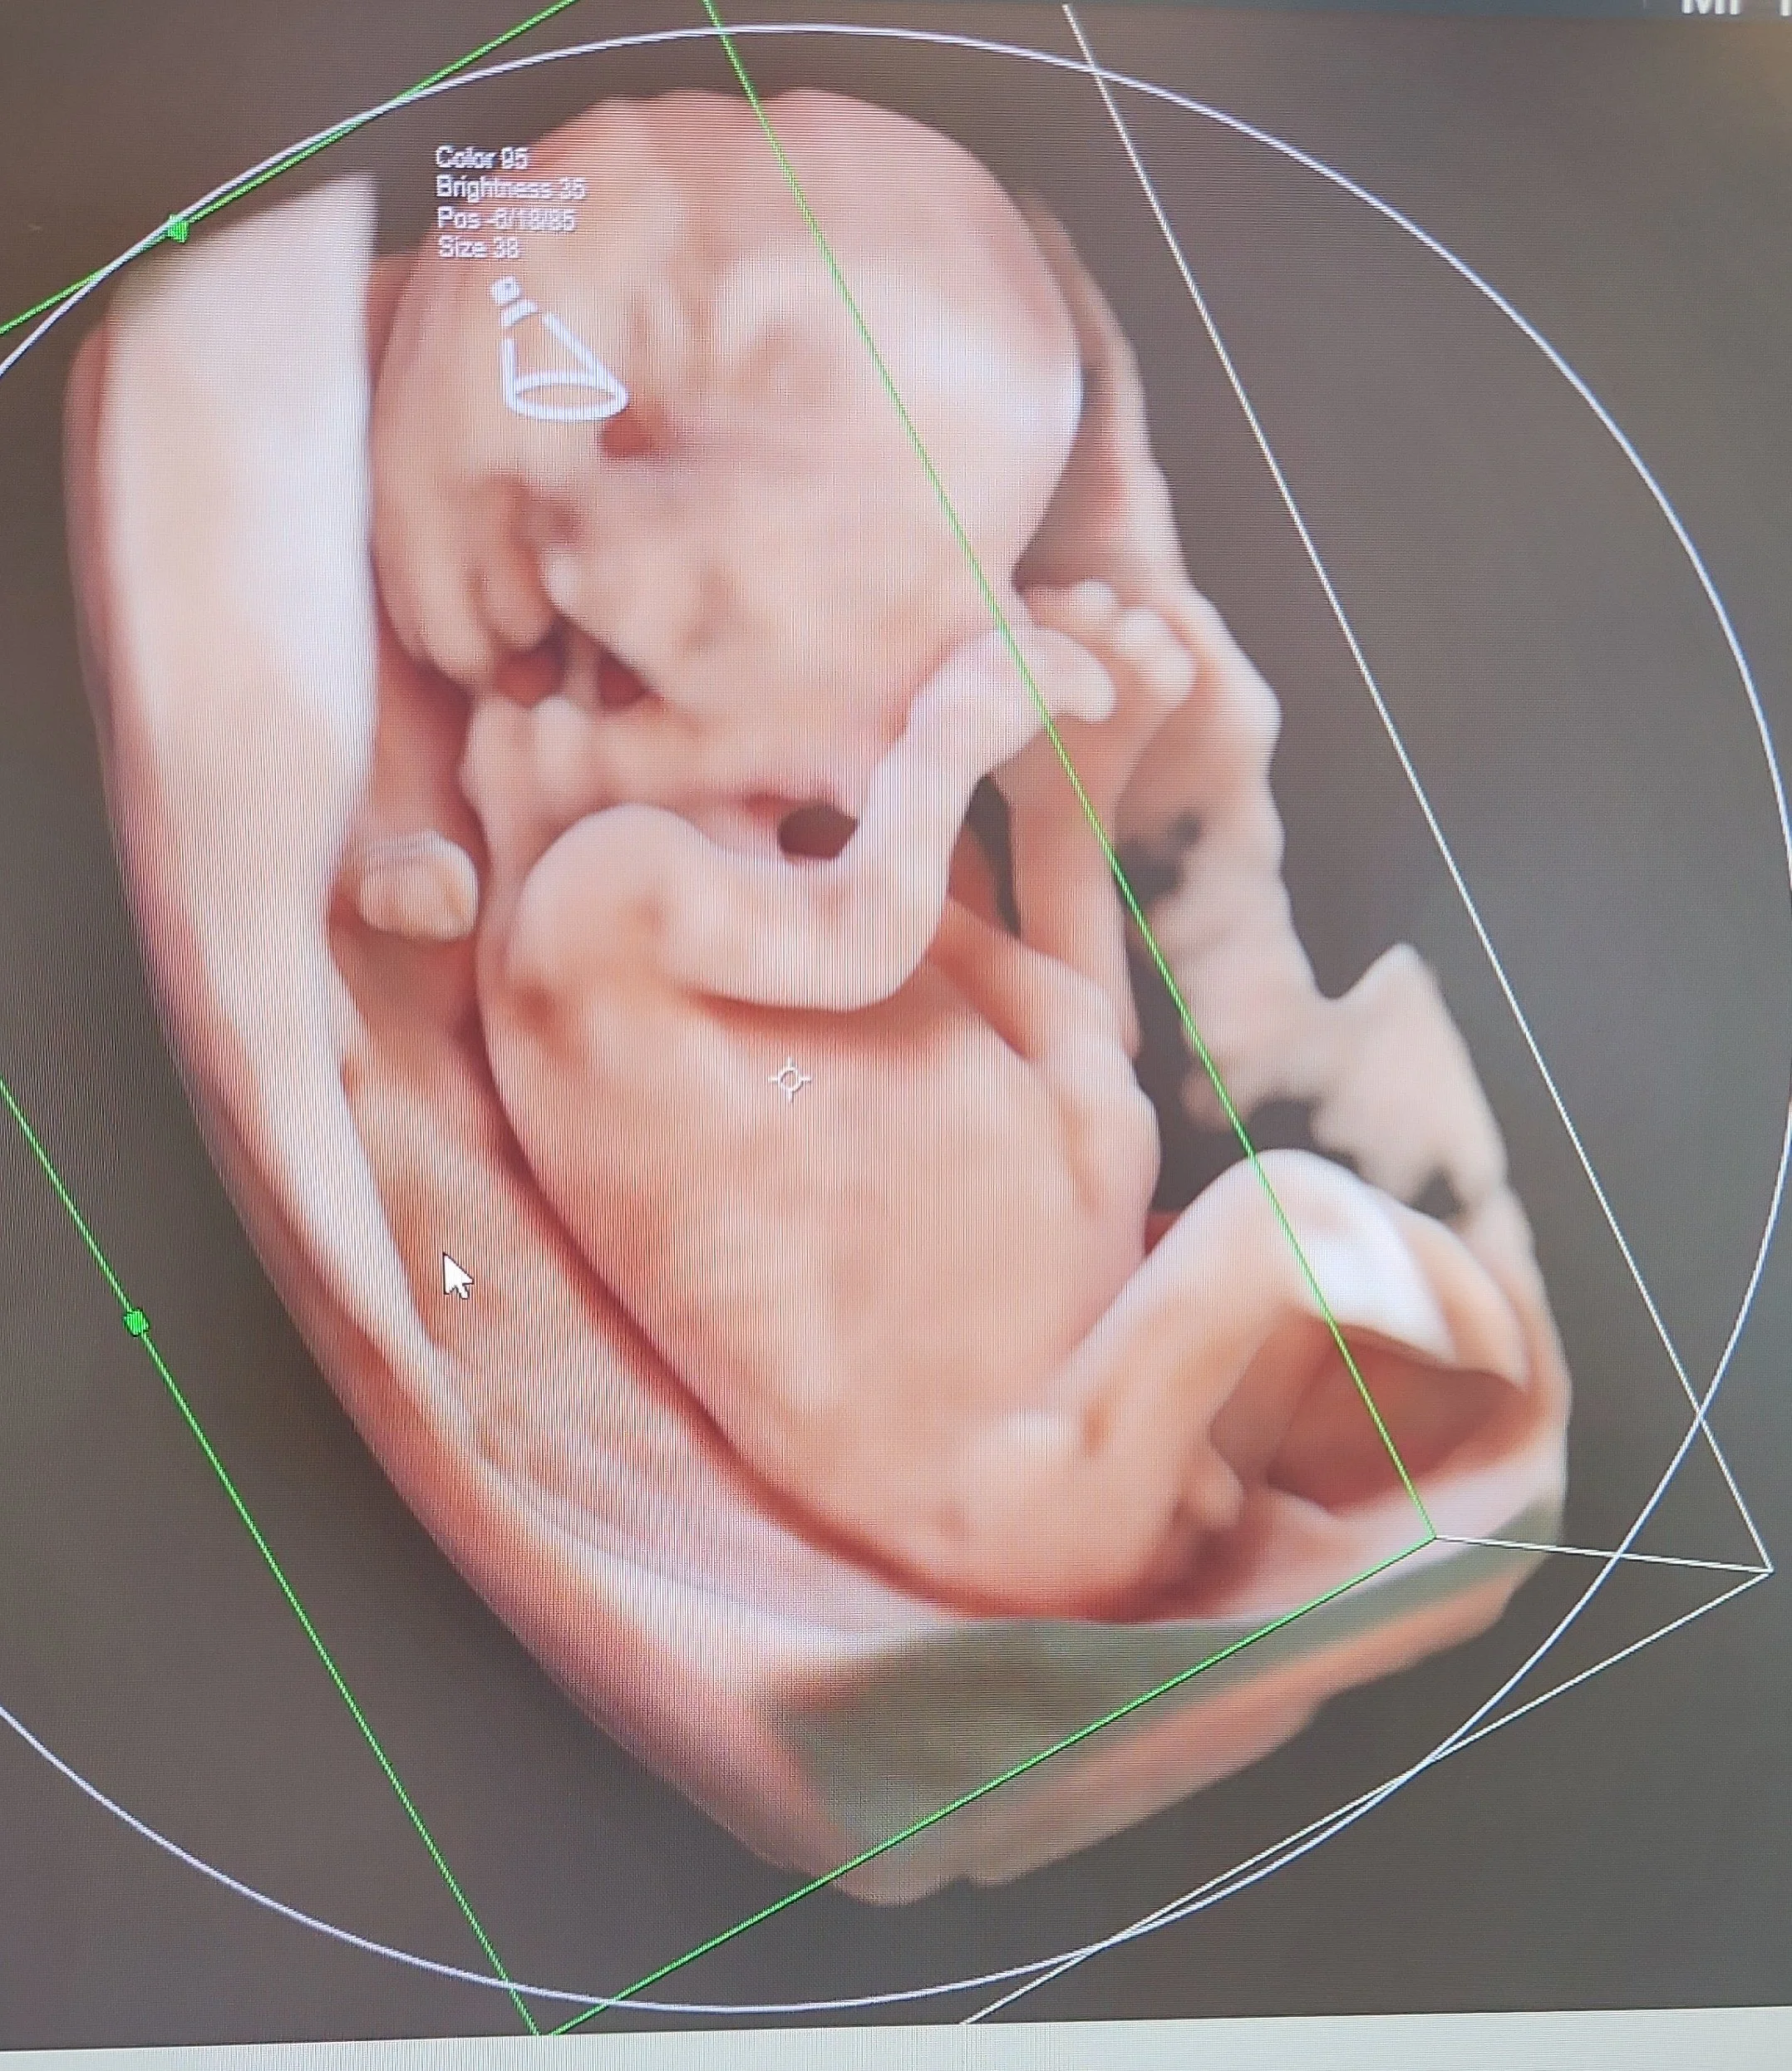

Cette échographie détaillée est réalisée entre 21 et 24 semaines d’aménorrhée. Le foetus pèse alors environ 400 à 600 grammes. C’est le moment idéal pour examiner en détail ses organes et vérifier leur bon développement. Le sexe foetal peut être révélé aux parents s’ils le souhaitent, et certaines malformations peuvent être dépistées.

Galerie d'échographies